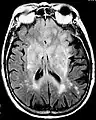

Postcontrast FLAIR of a case of meningitis. It shows enhancement of meninges at the tentorium and in the parietal region, with evidence of dilated ventricles.